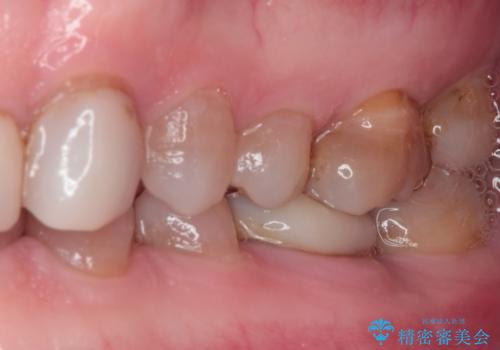

- 前歯の変色や欠損による隙間を気にして来院された患者様です。

上顎前歯は樹脂による変色を覆い隠す処置が行われていましたが、汚れが溜まりやすく厚みも増している状態でした。

上顎前歯は樹脂を外し、下顎前歯の隙間はそれぞれの歯を大きくするように補綴治療を行うことで隙間を埋めることとしました。